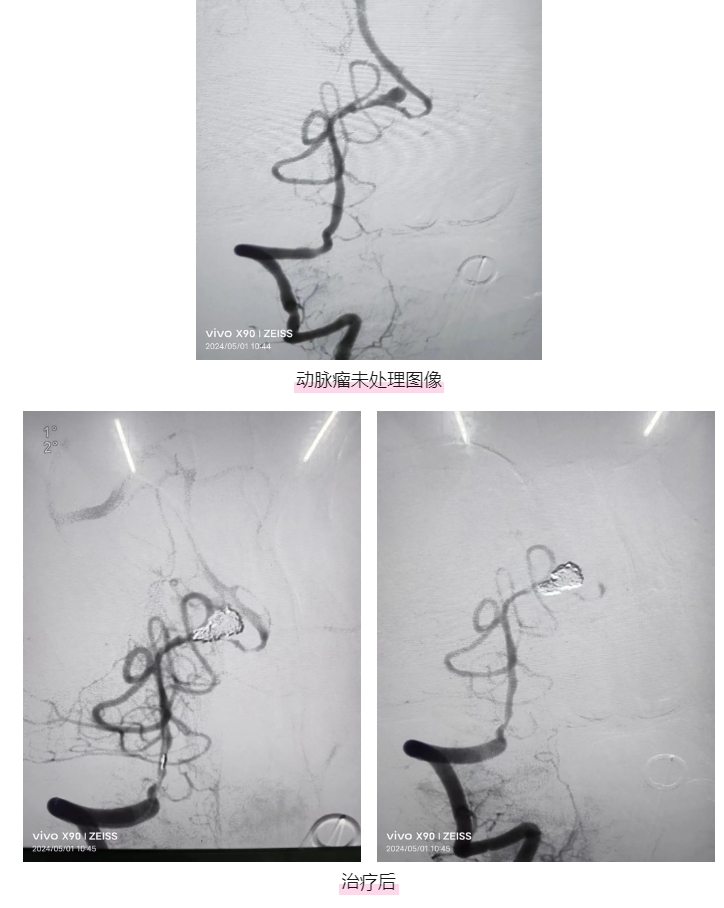

为了不辜负患者家属的殷切信任,江顺福立即联系到麻醉科行全脑血管造影术。造影显示为动脉瘤,给予动脉瘤弹簧圈介入栓塞治疗,解除出血病因。但因患者出血量非常大,影响到呼吸、血液循环,危及生命。

于是江顺福立即将患者转移至神经内科NICU行微创双侧侧脑室引流、腰穿脑脊液释放,最大限度挽救生命。当晚,患者生命体征逐渐恢复正常,能说话、肢体可小幅度活动。

术后,经过医护团队8天的精心治疗和悉心护理,张先生拔除气管插管,四肢活动、语言表达正常,生命体征平稳,转入普通病房继续治疗,于5月27日出院。